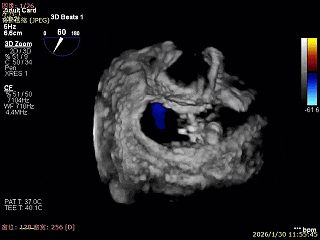

3D Enface 2区及3区前叶脱向左房

3D Enface 可见反流由2区3区从前后冲出